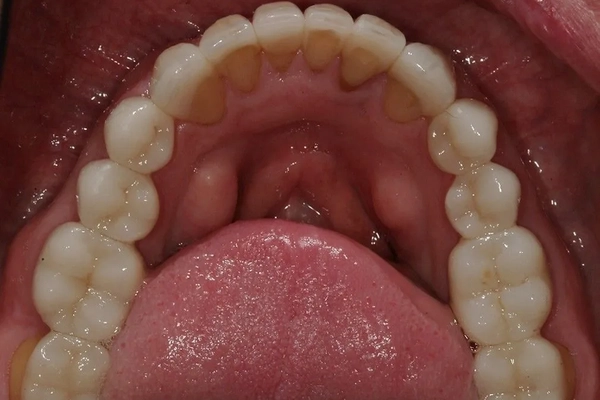

After

Mercury-Free Dentistry Before and Afters at Suite Dental